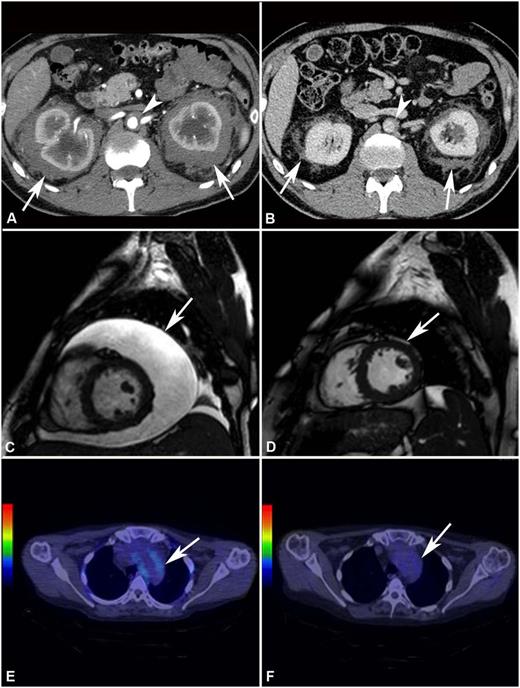

The remaining 8 patients showed PRs of at least one involved site. Retroperitoneal lesions regressed partially in 4/8 cases and completely in 1/8 (Figure 1 and supplemental Figure 2): at last follow-up, only 2 patients had double-J ureteral stents, and the patient with repeat bowel obstructions (patient #1) no longer developed such complications. Cardiovascular lesions improved in 3/4 cases: the 2 patients with severe pericarditis (one of whom was previously described28 ) underwent pericardiocentesis and remained free of pericardial effusion over the entire follow-up (Figure 1). Bone disease usually remained stable, although an improvement at 99Tc-scintigraphy was observed in 3 cases (Figure 2). CNS lesions progressed in patient #6 and stabilized in patient #3, whereas in patient #7 there was no recurrence of the surgically excised brain mass, and the remaining nodules showed partial regression (supplemental Figure 3). Lung involvement stabilized in all cases. The outcome of the remaining disease manifestations is reported in Table 2. Systemic symptoms improved in most patients; the only patient who experienced persistent systemic manifestations was patient #8. C-reactive protein levels also tended to decrease over time (supplemental Figure 4).

Response to treatment assessed by different imaging modalities. (A) Abdominal CT performed before treatment and (B) after 4 years of SRL and PDN treatment in patient #2. The scans show marked shrinkage of peri-renal (arrows) and peri-aortic fibrosis (arrowhead). (C) Cardiac MRI (T2-weighted, fat-saturation sequence, sagittal view) performed before treatment and (D) after 12 months of treatment with SRL and PDN in patient #10. The scans show neither recurrence of pericardial effusion (arrow) (the patient had also undergone pericardiocentesis) nor signs of pericardial infiltration. (E) 18F-FDG PET-CT performed before and (F) after 12 months of treatment with SRL and PDN in patient #10. The scans (axial view) show disappearance of 18F-FDG uptake at the thoracic aorta level (aortic arch) (arrow).

PET-CT was positive at baseline (especially at the bone, vascular, soft-tissue, and retroperitoneal levels) in 5/7 patients studied (Table 2): of these, 1 patient achieved a CMR (Figure 1), 1 a PMR, 1 SD, 1 was lost to follow-up before follow-up PET-CT was performed, and 1 did not repeat PET-CT because of overt clinical progression.